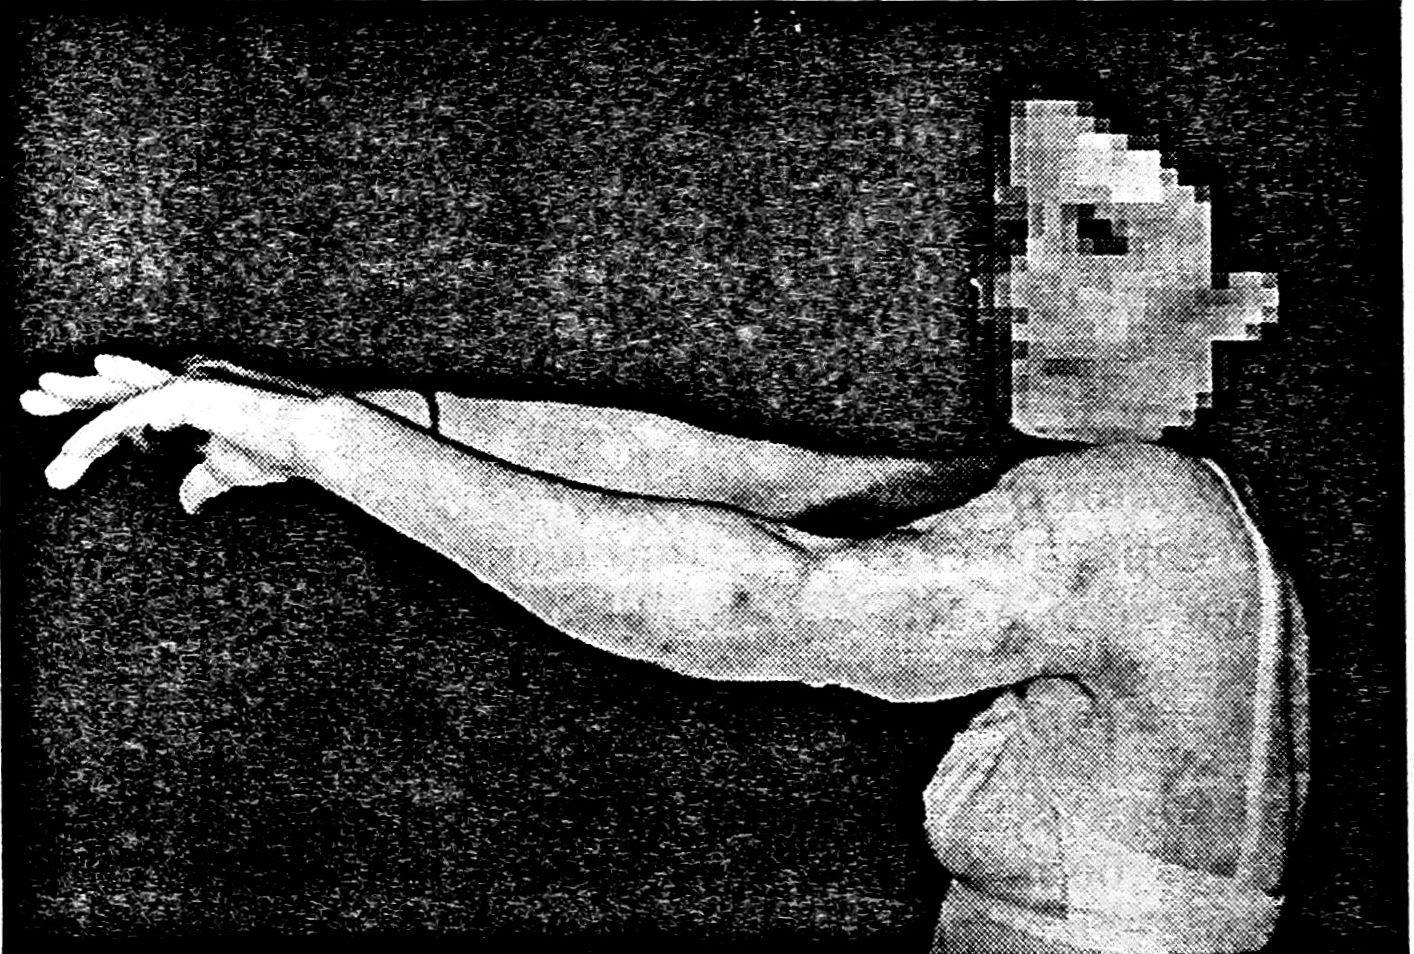

Через 3 мес наступила полная консолидация трансплантата с реципиентной костью (рис. 4). В процессе лечения проводилась электростимуляция перемещенной широчайшей мышцы спины. Функция ее сохранилась, движения в локтевом суставе восстановились (рис. 5).

Рис. 5. Функциональный результат.